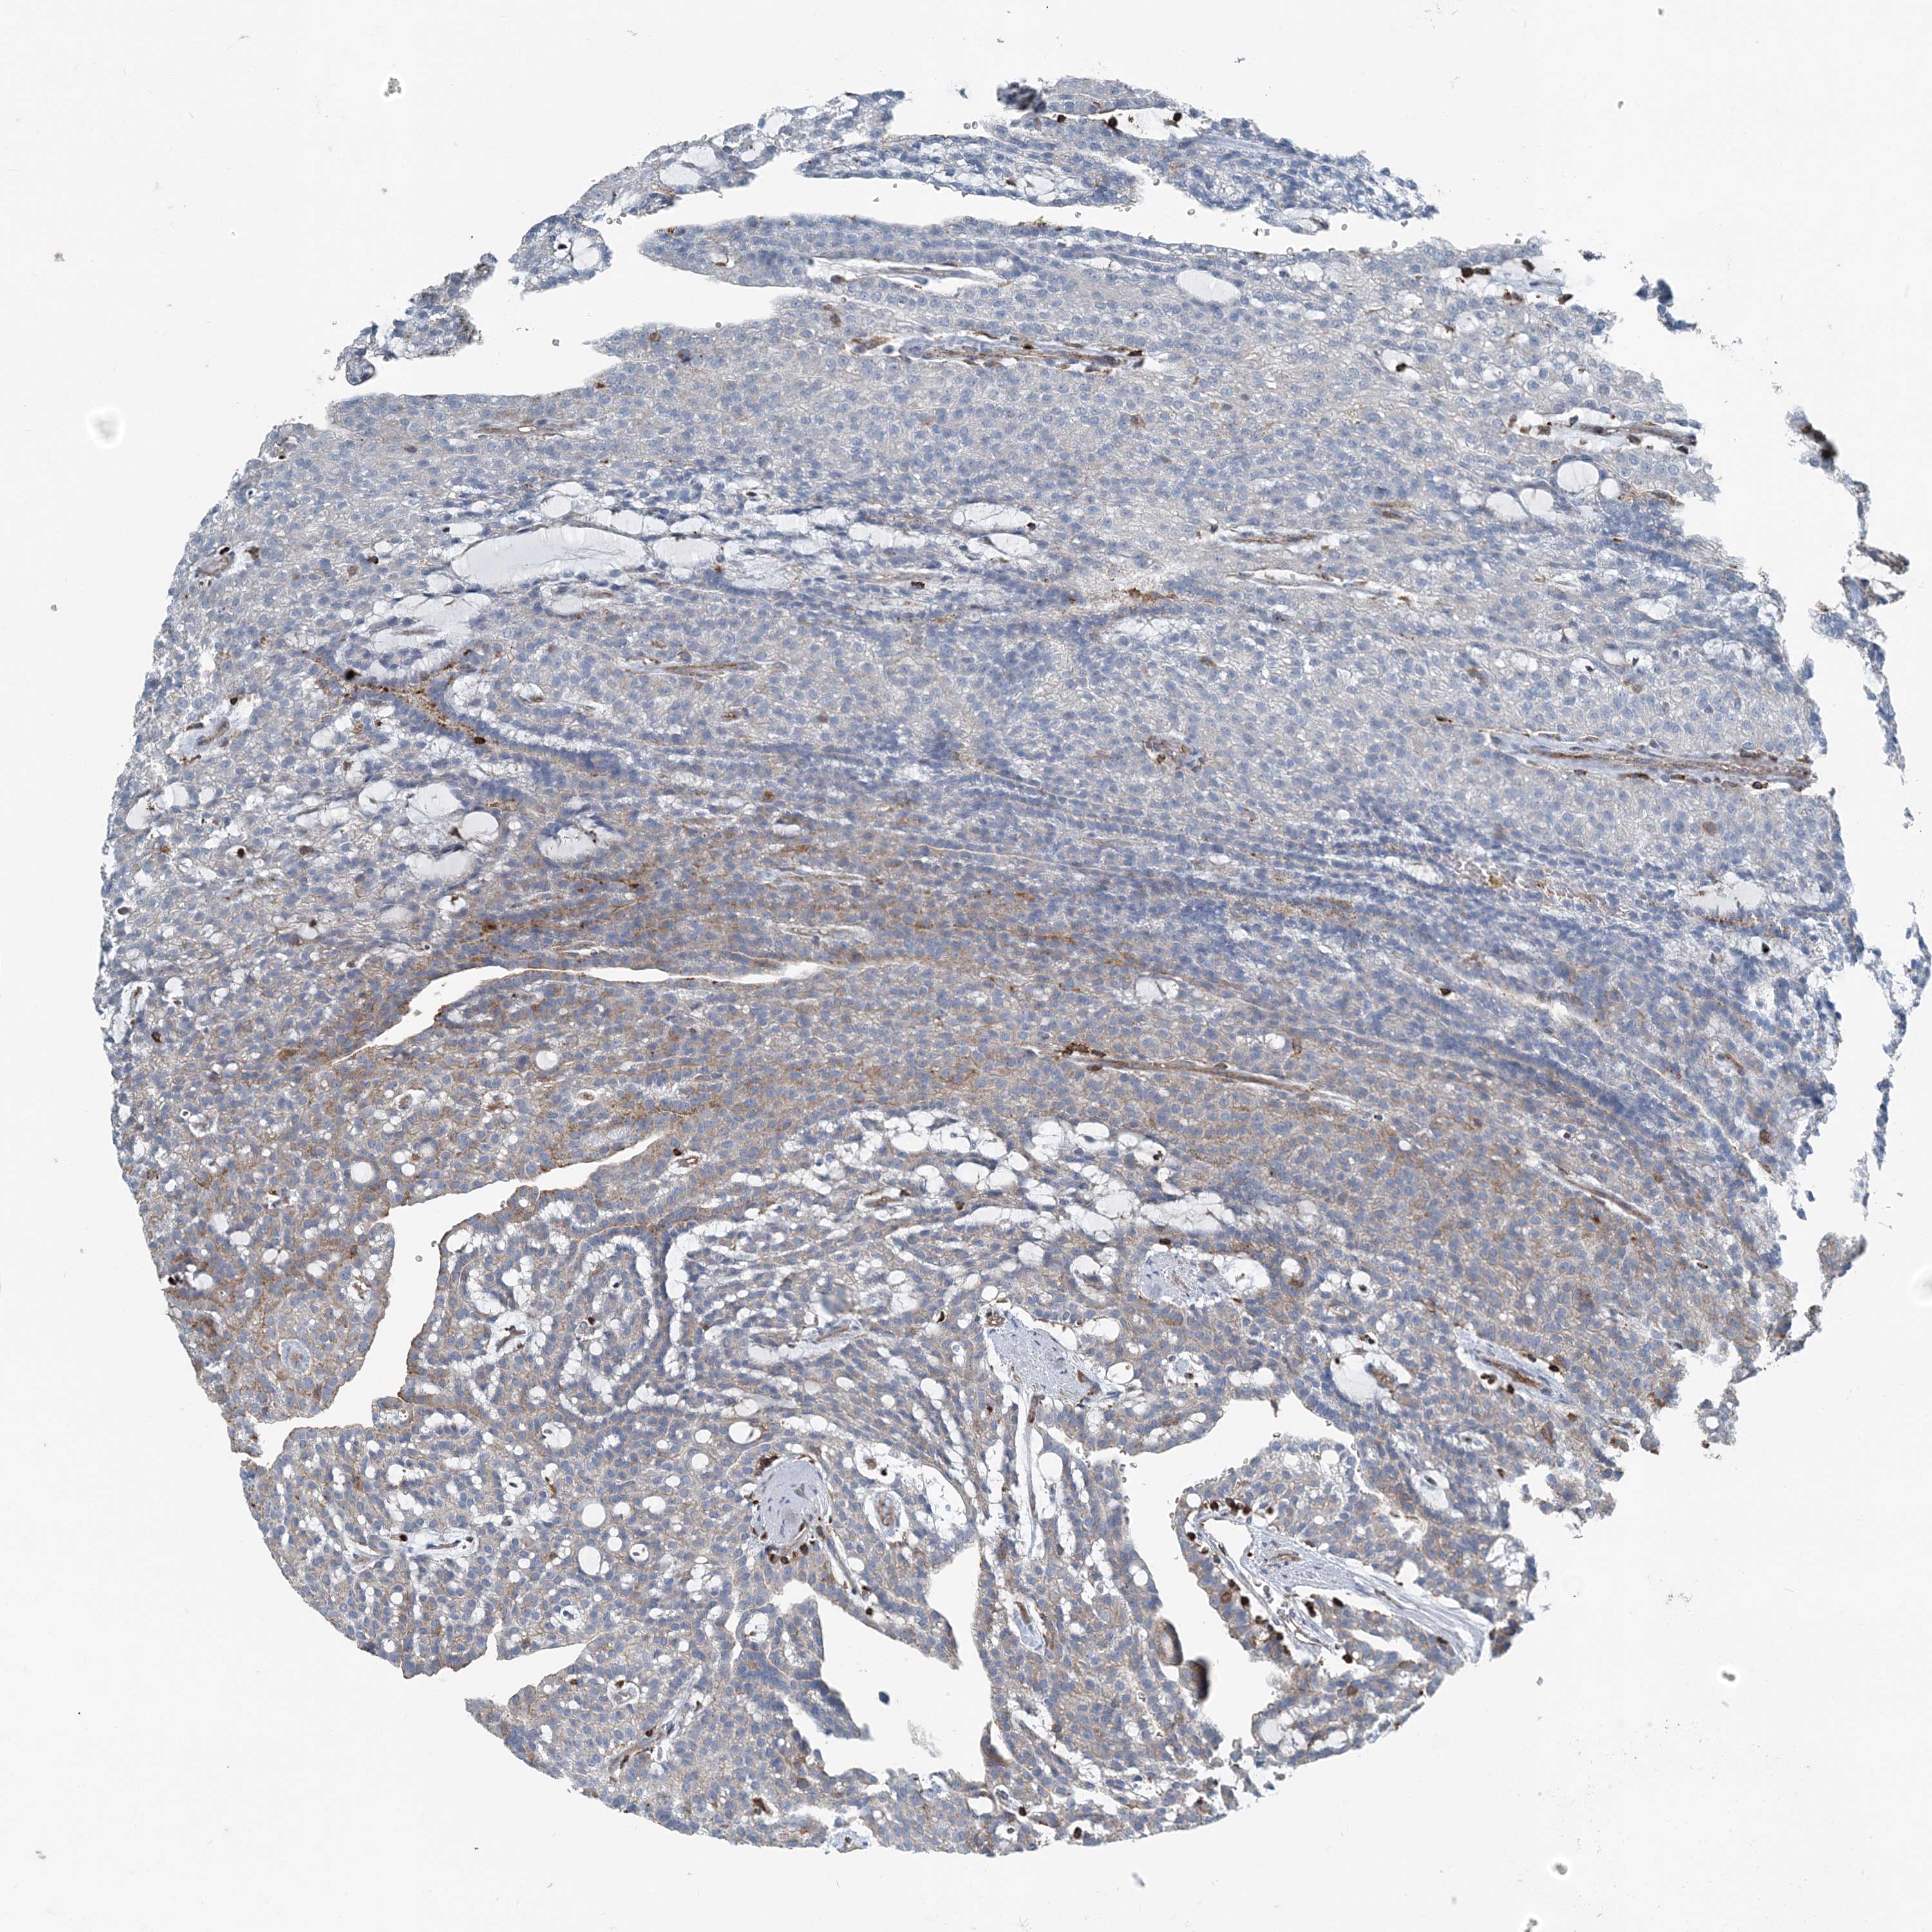

KIDNEY RENAL PAPILLARY CELL CARCINOMA (TCGA) - Interactive survival scatter ploti

The Survival Scatter plot shows the clinical status (i.e. dead or alive) for all individuals in the patient cohort, based on the same data that underlies the corresponding Kaplan-Meier plots. Patients that are alive at last time for follow-up are shown in blue and patients who have died during the study are shown in red.

The x-axis shows the expression levels (FPKM) of the investigated gene in the tumor tissue at the time of diagnosis. The y-axis shows the follow-up time after diagnosis (years). Both axes are complimented with kernel density curves demonstrating the data density over the axes. The top density plot shows the expression levels (FPKM) distribution among dead (red) and alive patients (blue). The right density plot shows the data density of the survived years of dead patients with high and low expression levels respectively, stratified using the cutoff indicated by the vertical dashed line through the Survival Scatter plot. This cutoff is automatically defined based on the FPKM cutoff that minimizes the p-score. The cutoff can be changed by dragging the vertical line or by entering a cutoff value in the square labeled "Current cut-off".

Under the Survival Scatter plot the p-score landscape (black curve; left axis) is shown together with dead median separation (red curve; right axis). Dead median separation is the difference in median mRNA expression between patients who have died with high and low expression, respectively. It is calculated as follows: median FPKM expression of dead patients with high expression - median FPKM expression of dead patients with low expression. This is intended to aid the user in visually exploring custom cutoffs and the associated p-scores and dead median separation.

Individual patient data is displayed and can be filtered by clicking on one or more of the category buttons on the top of the page. Categories describing expression level and patient information include: high, low, alive, dead, female, male and tumor stages. The scale of the x-axis can be toggled between linear and log-scale by clicking on the "x log" button. Mouse-over function shows TCGA ID, patient information and mRNA expression (FPKM) for each patient.

& Survival analysisi